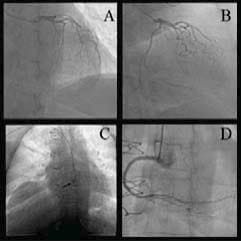

We present the case of a 58-year-old female who underwent HTx for end-stage heart failure secondary to ischemic dilated cardiomyopathy 14 years before. The patient first presented to her family physician for epigastric discomfort accompanied by intense fatigue, dizziness, and generalized weakness. She was prescribed antacids and no further investigations were performed. Due to persistence of symptoms, the patient presented the next day to the Emergency Department of our hospital, approximately 24 hours after symptoms onset. Her medical history included arterial hypertension, obesity, and dyslipidemia. The patient was on long-term therapy with immunosuppressive agents (cyclosporine and mycophenolate mofetil), cotrimoxazole, calcium channel blocker, loop and mineralocorticoid antagonist diuretics, and a statin. Physical examination showed a body mass index of 37.1 kg/m2 and a heart rate of 70 beats per minute; her blood pressure was 110/90 mmHg; cardiac and pulmonary examinations were unremarkable. The electrocardiogram (Figure 1) revealed normal sinus rhythm with right bundle branch block (already known), STsegment elevation in the inferior leads, alongside with pathological Q waves in the same territory, and depressed ST-segment in leads I and aVL, with inverted T waves in leads V3 to V6. Cardiac necrosis biomarkers showed elevated troponin I (27.1 ng/ml), creatin kinase (3.000 IU/l), and creatin-kinase myocardial band (236 IU/l) levels. Transthoracic echocardiogram revealed hypokinesia of the left ventricular inferior wall, with a preserved left ventricular ejection fraction of 45%, grade I diastolic dysfunction, and moderate mitral regurgitation. Based on these findings, the patient was diagnosed with acute inferior ST-segment elevation myocardial infarction (STEMI), and treated, according to current practice guidelines, with dual antiplatelet therapy (DAPT), low-weight molecular heparin, statin, and beta-blocker. Coronary angiogram revealed no atherosclerotic lesions of the left coronary artery (Figure 2 A and B), and proximal occlusion of the right coronary artery as culprit lesion (Figure 2 C). A drug-eluting stent was successfully implanted at the site of the lesion (Figure 2 D). The patient was discharged seven days later, after an uneventful evolution.

Figure 2. Coronary angiogram. Left coronary artery in right anterior oblique cranial view (A) and right anterior oblique caudal view (B). Complete occlusion of the right coronary artery (arrow) in left anterior oblique view (C), and opening of the artery after stent deployment in left anterior oblique view (D).